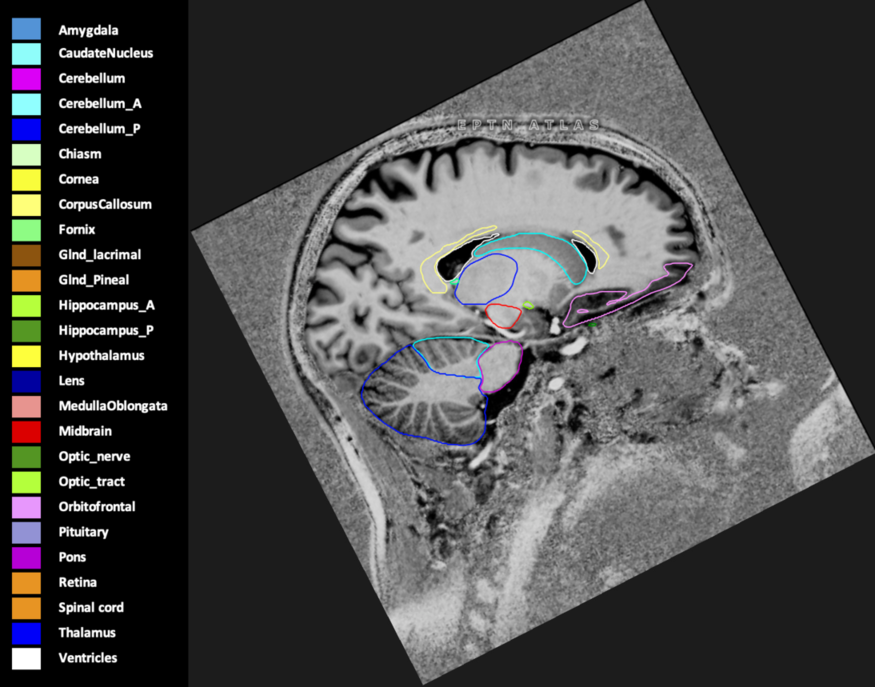

Eekers et al. have published an international neurological atlas for contouring of organs at risk in consensus with the European Particle Therapy Network (EPTN) in 2018 and an update in 2021. The purpose of this consensus atlas is to decrease inter- and intra-observer variability in delineating OARs relevant for neuro-oncology.

Included are all OARs known to be relevant for radiation-induced toxicity in neuro-oncology: brain, brainstem (midbrain, pons, medulla oblongata), chiasm, cerebellum (anterior & posterior), cochlea, cornea, hippocampus (anterior & posterior), hypothalamus, lens, lacrimal gland, optic nerve, pituitary, skin, and vestibular & semicircular canals. To further facilitate research on cognition, vision and radiological changes after irradiation of the brain, potential clinically-relevant OARs are included: amygdala, caudate nucleus, cerebellum (anterior & posterior), corpus callosum, fornix, macula, optic tract, orbitofrontal cortex, periventricular space (PVS), pineal gland, and thalamus.

Three-dimensional delineation of the 25 consensus OARs for neuro-oncology are shown on CT (WW/WL 120/40, 3000/600), 3T MR images, (T1Gd, T2FLAIR 1mm) and 7T MR (MP2RAGE 0.7 mm). All are presented in transversal, sagittal and coronal view.